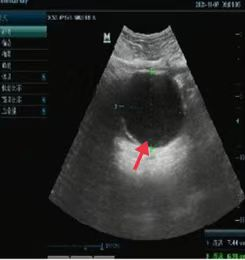

04、**男士,60岁

于2023年10月24日在邯郸仁泰东区体检,腹部彩超检查提示:肝内见多个无回声,较大位于右叶,大小约1.2*1.1cm,边界清,外形规则,右叶另见多个实性等回声团,较大约11.4*7.8cm,中央可见液化。2023年10月25日通知客户到三甲医院进一步检查。2023年11月25日跟踪回访,客户家属反馈在邯郸市中心医院进一步检查考虑肝癌,现已在中心医院住院治疗。